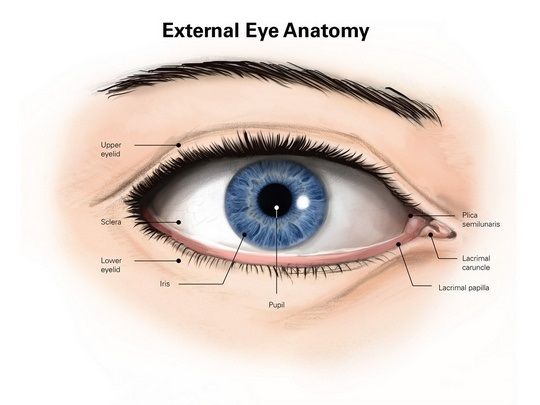

The human body is incredibly complex. Make it understandable with a diagram from Encyclopaedia Britannica. https://t.co/nqXY2hnYSW